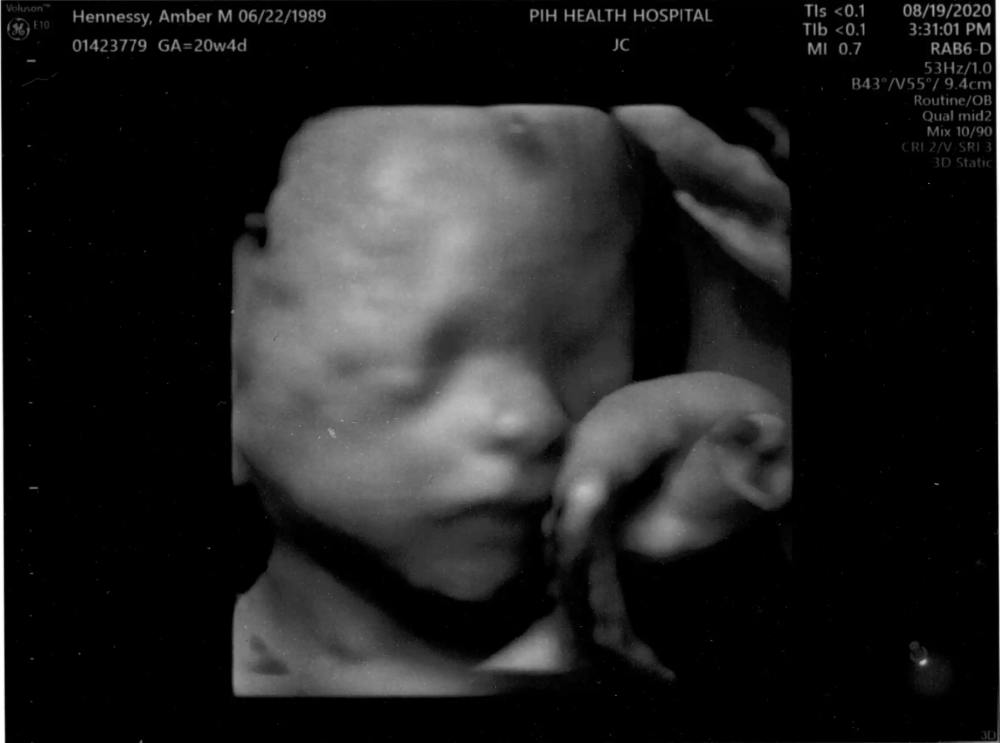

August DnA Baby Registry! August 23, 2020 BabyFamily A New Pirate for the Crew August 19, 2020 BabyFamily Surprise it’s a Girl! August 19, 2020 BabyFamily Archives Archives Select Month February 2021 (1) August 2020 (3)